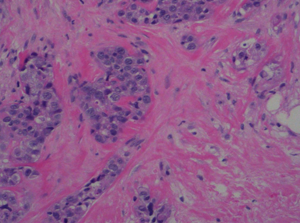

Prostate-Cancer

Prostate Cancers